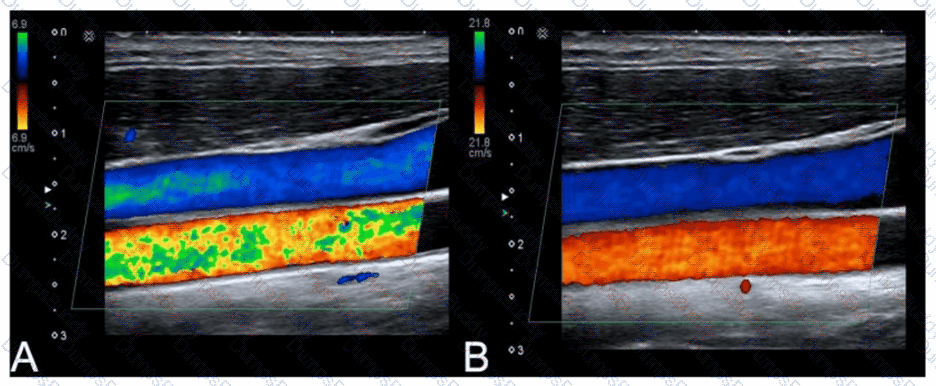

Which adjustment resulted in the change from image A to image B?

SPI Question 22

Options:

A.

Increased transmit frequency

B.

Increased scale

C.

Decreased color gain

D.

Decreased acoustic power